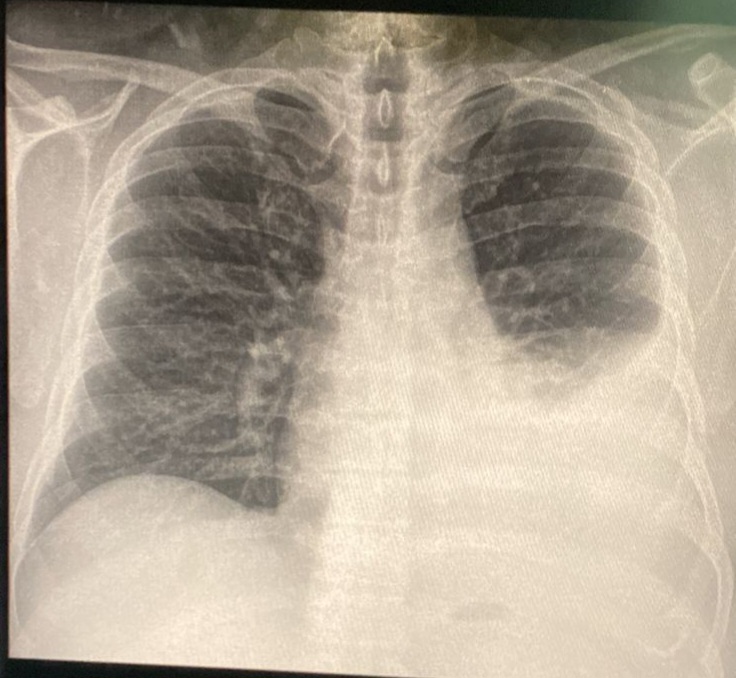

draurtecho Jul 17, 2024 La tuberculosis puede presentarse de muchas formas y dar síntomas clínicos como fiebre tos, pérdida de peso. Una de las presentaciones más frecuente a nivel pleural es el derrame pleural y a nivel pulmonar podría presentarse en forma de nódulos, como se muestra en las siguientes imágenes. No Comments InNeumología